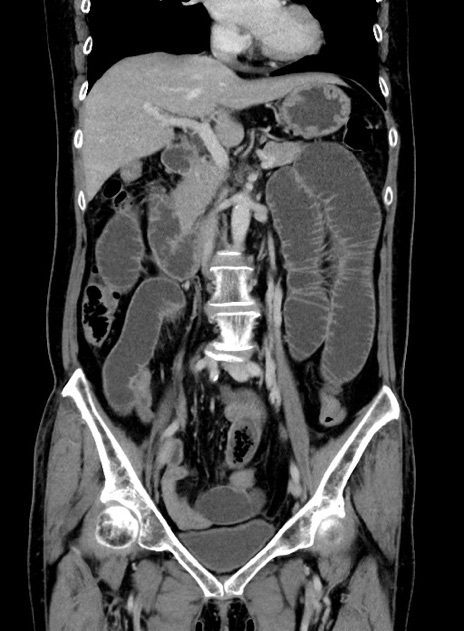

症例9(冠状断像)

【症例】 60歳代女性

【主訴】むかつき、みぞおちの痛み

【現病歴】3日前よりむかつきがあり、食事がとれない。

【既往歴】糖尿病

【身体所見】発熱なし、心窩部圧痛軽度あるも、腹膜刺激症状なし。

【データ】WBC 7400、CRP 1.92